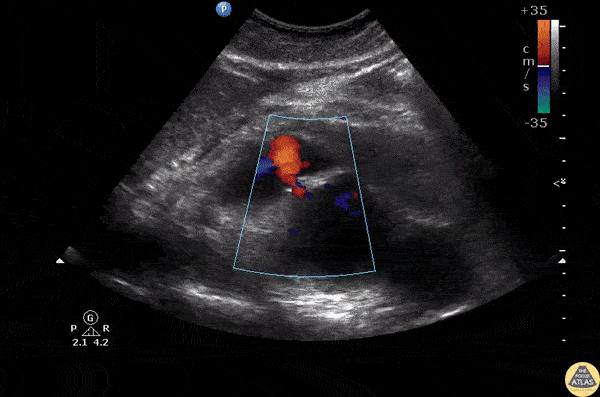

Aorta - Ruptured AAA

Sagittal view of an abdominal aortic aneurysm with a hemorrhage anterior to the aorta. Be sure to distinguish a AAA from a dissection by assessing the abnormal wall motion seen at the site of rupture. Image courtesy of Robert Jones DO, FACEP @RJonesSonoEM Director, Emergency Ultrasound; MetroHealth Medical Center; Professor, Case Western Reserve Medical School, Cleveland, OH View his original post here